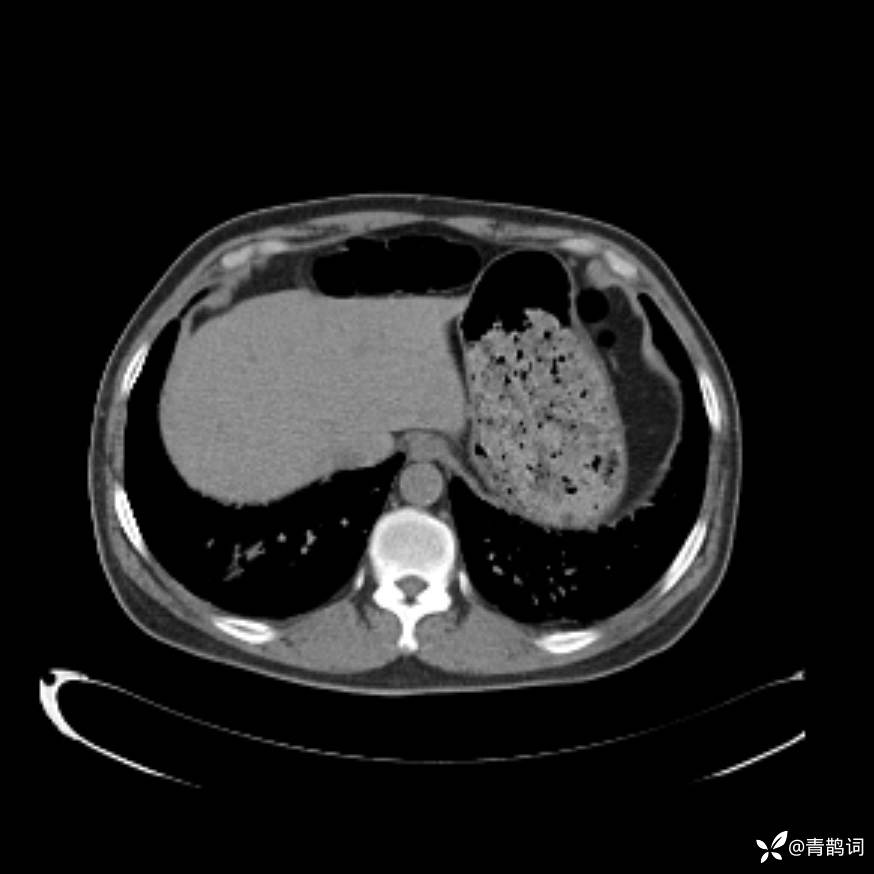

患者年龄:30岁。

患者性别:男。

简要病史:左颜面部肿胀2年,反复咳嗽咳痰,逐渐加重。

辅助检查

结合病史及影像学表现,期待评论区各位老师各抒己见~